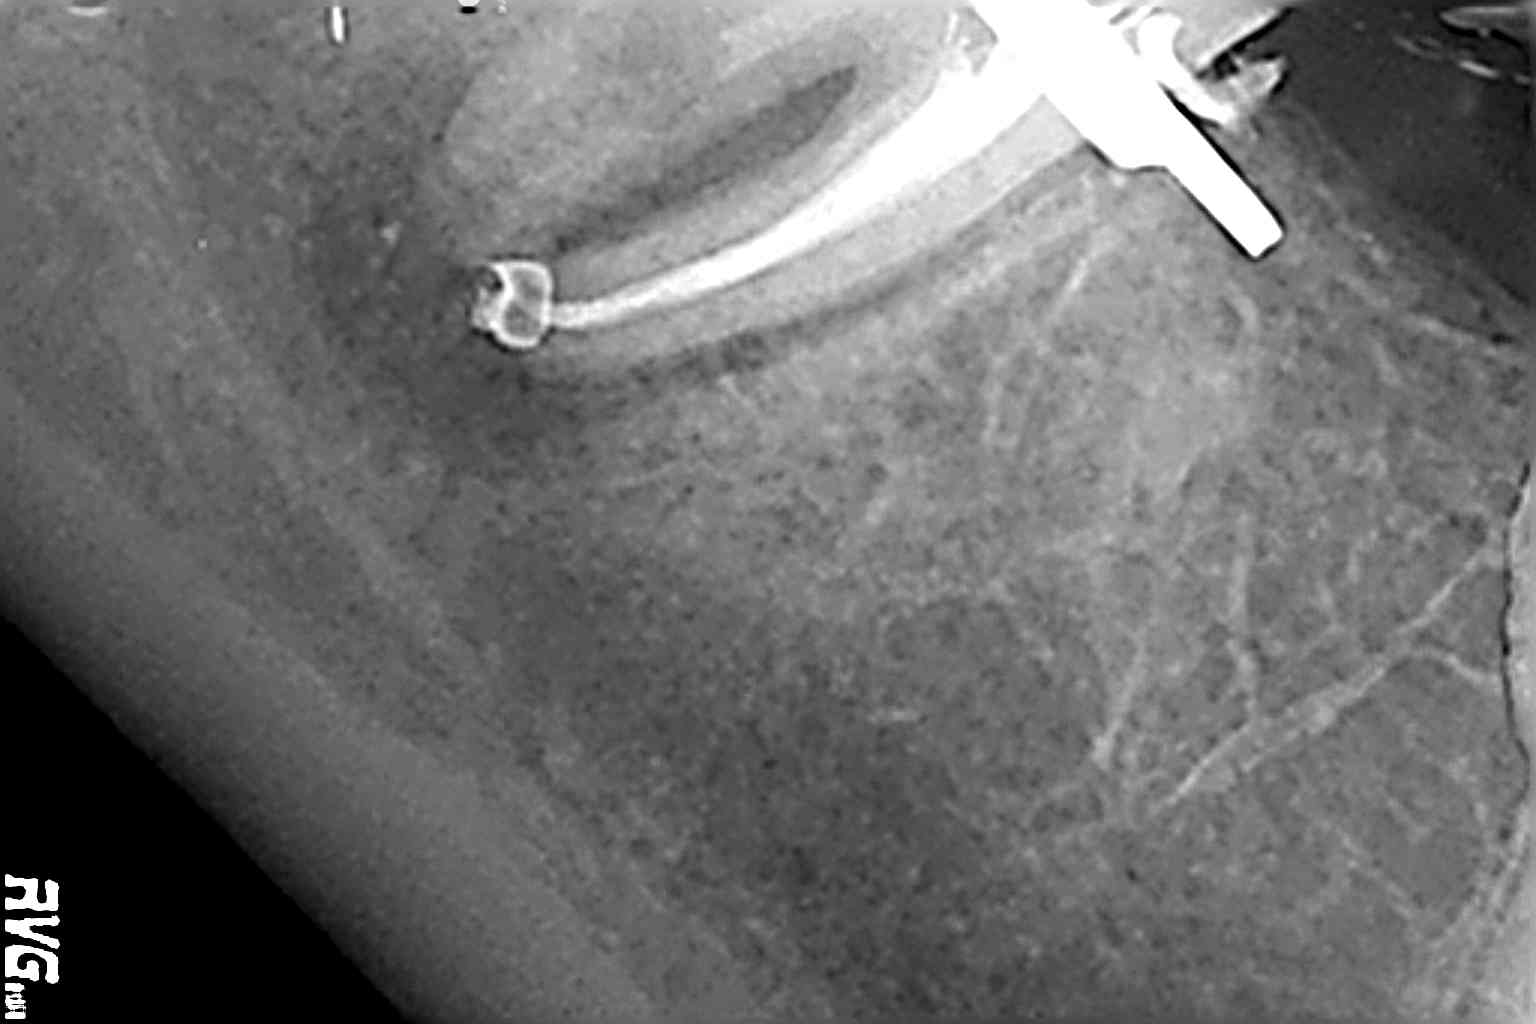

Hemos llamado a revisión a la paciente en varias ocasiones ( 6 meses y 9 meses)

(revision a los 6 meses) (revisión a los 9 meses)

Como podemos observar, la lesión periapical ha regenarado: